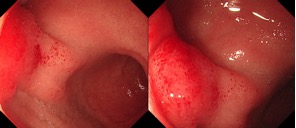

一个月前,患者刘阿姨(化名)无明显诱因出现左上腹持续性隐痛,自行服药未见好转,随后更出现了便血症状。在当地医院进行腹部CT检查时发现,其十二指肠球部可见一高密度影,走行方向从腔内延续至腔外(图1)——这一征象提示异物已穿透肠壁,情况十分危险。

图1腹部CT:十二指肠球部可见一高密度影,

走行方向从球腔内延续至腹腔(红色箭头)